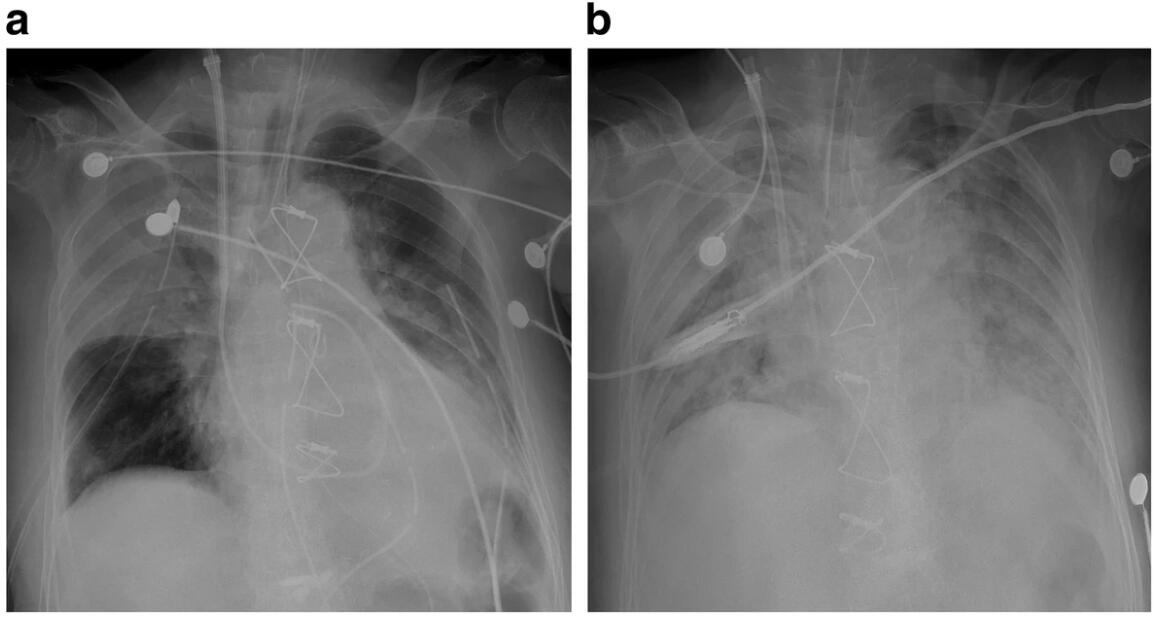

重医附二院胸心外科成功开展多例全动脉化冠脉搭桥手术胸心外科团队率先在重庆市开展了全动脉化冠脉搭桥和保留全部瓣下结构的二尖瓣替换手术,成功开启了市内心脏疾病治疗的新篇章。截至目前,该团队已连续开展多例全动脉化冠脉搭桥手术,以动脉血管作为旁路血管,实现了心脏患者更多的治疗可能。 2024年12月,52岁的向先生感到每...

76岁复杂冠心病患者成功“闯关” 全动脉搭桥开辟长效“心”路为何选择全动脉化心脏搭桥?胸心外科副主任医师张沛解释,传统大隐静脉桥随时间推移易病变狭窄,而动脉血管凭借坚韧特性,10年通畅率可超90%,能大幅降低二次手术风险,显著提升心肌供血与心脏功能,延长患者生存期并改善生存质量。 复杂冠心病严重威胁高龄患者生命健康,尤其当常...

̄□ ̄|| 男子不按时吃药致“心路”堵塞 株洲恺德医院搭桥手术助他重获“心...红网时刻新闻10月15日讯(通讯员 黎婕妤)58岁男子确诊冠心病,不按时吃药,导致自己心血管堵了。株洲恺德心血管病医院心胸外科团队为其开展体外循环下冠状动脉旁路移植手术,助他重获“心生”。手术资料图。58岁的谢先生(化名)一年前总感觉心脏不舒服,反复地胸闷胸痛,休息一会...